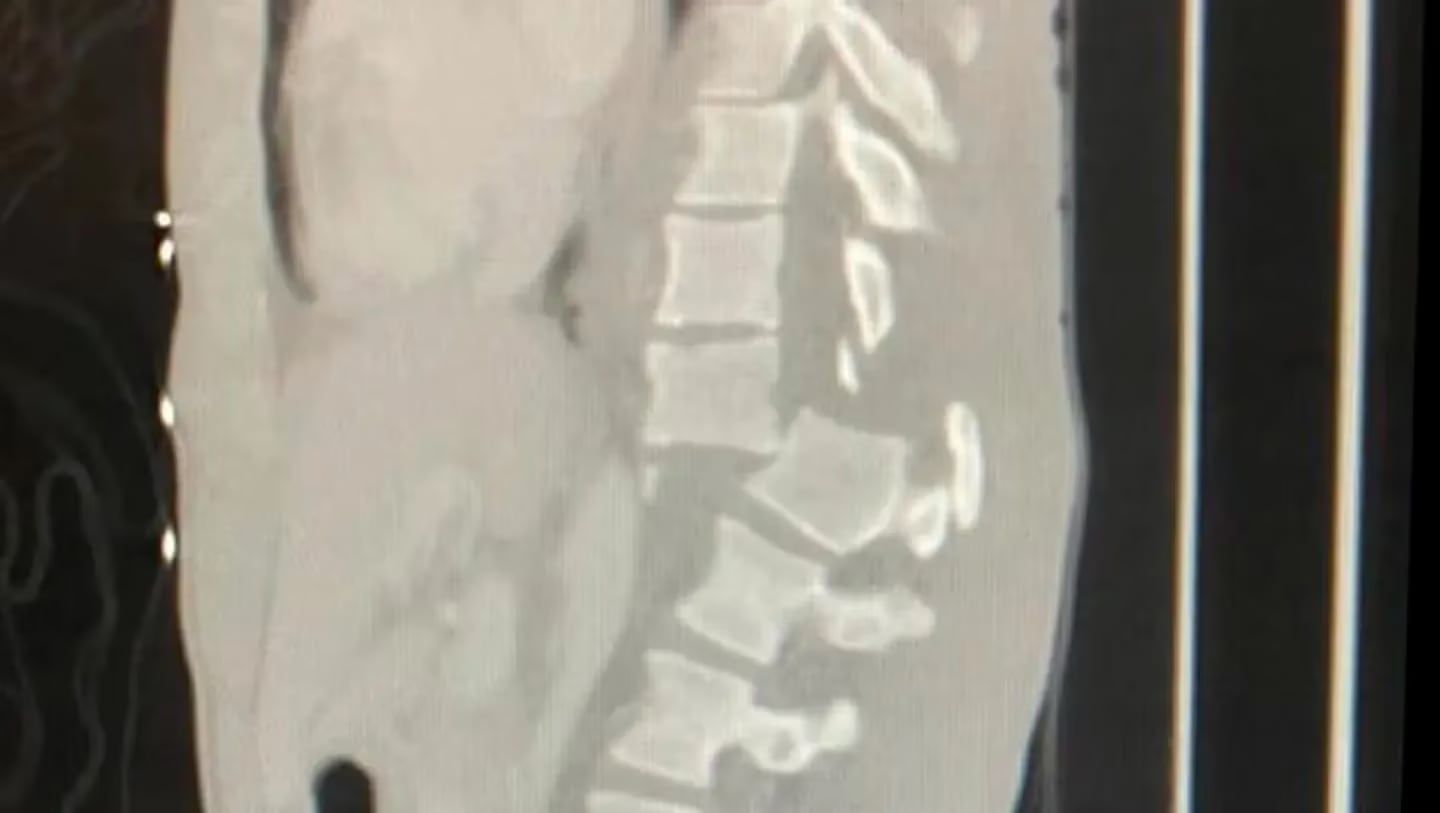

“Estaba en las piscinas naturales de Olivine y una gran ola me golpeó, me hizo desplomarme sobre las rocas. Me fracturé la columna y tuve que operarme de emergencia”, agregó.

Si bien permanece “estable”, Facundo aseguró que aún no logra sentir la parte inferior del cuerpo y de momento usa una silla de ruedas.